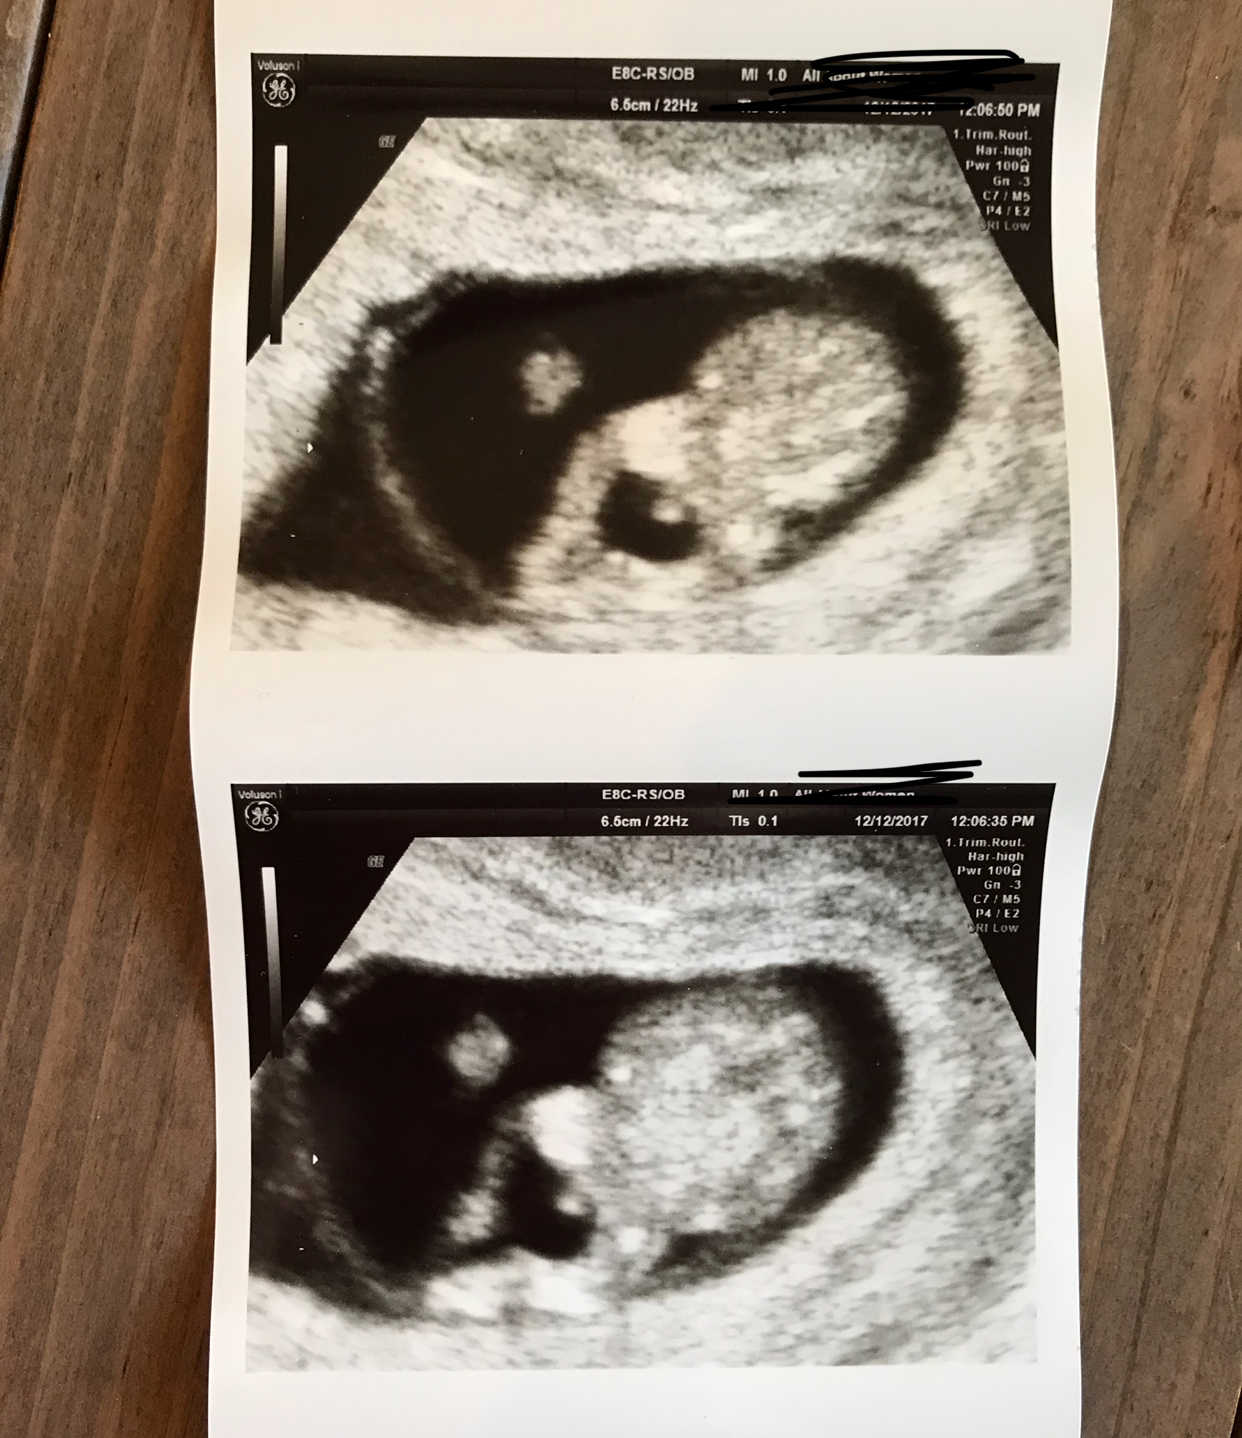

Hi everyone, I have 3 boys and I’m pregnant with number four. I’m 13.5 weeks now but was 10.5 weeks at the time of this appointment. My OB pointed out boy parts to us and was certain in her assessment but I just can’t give up hope. It was so early. Here are the shots. I know potty shots aren’t reliable this early, but she seemed so confident and it looks so big! Any advice is appreciated. Thanks! Attachment 38552